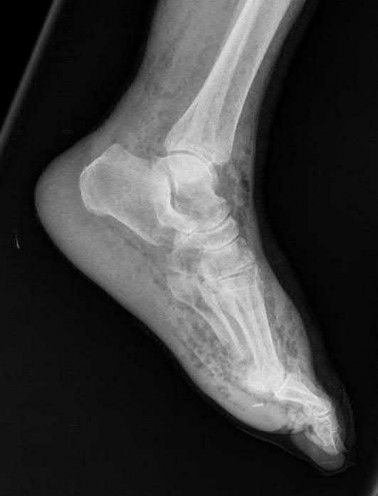

A 25-year-old male sustains an ankle fracture dislocation and undergoes open reduction and internal fixation. He returns to clinic five months following surgery complaining of continued ankle pain and instability with weight bearing. His immediate post-operative AP radiograph is seen in Figure A. Which of the following could have prevented this patient from developing persistent pain?

The patient presents with continued ankle pain and instability following open reduction and internal fixation. The radiograph in figure A demonstrates inadequate restoration of fibular length, likely leading to continued tibiotalar instability.